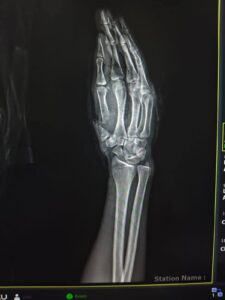

نجح فريق طبي متخصص بوحدة الجراحات الميكروسكوبية بمستشفى جامعة سوهاج، في إنقاذ شاب تعرض لبتر كامل بإصبع الإبهام، نتيجة اعتداء بسلاح أبيض.

أوضح الدكتور مجدي القاضي، عميد كلية الطب، أن الجراحة الميكروسكوبية الدقيقة استغرقت 6 ساعات متواصلة لتوصيل الأوعية الدموية والأعصاب المقطوعة تحت المجهر.

ثبت الفريق الطبي عظام الإصبع المبتور باستخدام أسلاك معدنية دقيقة، مما ساهم في استعادة الدورة الدموية بشكل طبيعي واستقرار حالة المصاب الصحية.